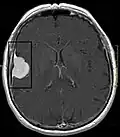

Meningeom im Röntgenbild des Schädels -

Kontrastmittel aufnehmendes Meningeom der linken Hemisphäre in der Computertomographie -

Großes Felsenbeinmeningeom in der Computertomographie -

Das bildgebende Verfahren der ersten Wahl ist beim Meningeom heute die Kernspintomografie, da dieses Verfahren den größten Weichteilkontrast besitzt und in typischen Fällen die sichere Diagnose eines Meningeoms ermöglicht. In T2-gewichteten Aufnahmen stellen sich verkalkte Meningeome im Gegensatz zu vielen anderen Tumoren als schwarze Masse (hypointens) dar, die dunkler als das umgebende Hirngewebe ist. Unverkalkte Meningeome können zur Umgebung isointens sein. Von anderen Tumoren unterscheiden sich Meningeome durch ihre Lage auf der Dura mater mit charakteristischen Ausläufern in die Dura (dural tails) und durch eine sehr intensive Kontrastmittelaufnahme. Die Computertomographie kann die Tumorverkalkungen sehr gut nachweisen. Konventionelles Röntgen und Angiographie haben heute nur noch eine untergeordnete Bedeutung.